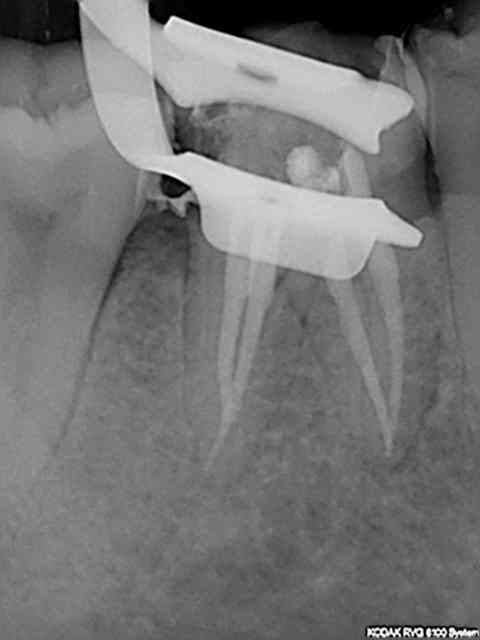

Dans le souci de ne pas irradier la patiente inutilement aucune autre radiographie gratuite d'un autre secteur n'est réalisée. Qui plus est le docteur chicot 29 étant équipé d'un capteur kodak 6100 ne peut pas réaliser de mordus rétro coronaires. Le Dr chicot 29 ayant une demi-heure devant lui réalise l'endo de 46 et cote donc Z6 fois 2 + SC 34 et met la patiente sous atb pour le 4 eme de la 36. Ce faisant il fait économiser à la caisse une C à 23 euros.-))

Meme en mode Bw rétro coronaire (capteur horizontal) il est impossible d'avoir toutes les molaires et prémolaires avec un kodak 6100 meme avec 4 clichés (Je ne comprend pas d'ailleurs le capteur semble couvrir toutes les dents) Il manque la 7 ou la 4. 8 clichés sont donc nécessaires (contre 12 en rétro alvéolaires capteur vertical).

Une rétro alvéolaire a été réalisé en sus pour la 37 bien qu'elle ne présente pas de "signes d'appels". Une magnifique endo révélée comme d'hab, le patient est éclairé quant à la survenue d'un éventuel problème. On peut se poser des questions également sur la pertinence des micro classes 1 amalgame sur 46 et 47 a moins que ce soit la conséquence d'un comportement "imaginatif " cher à Catherine M pour rentabiliser les soins opposables.